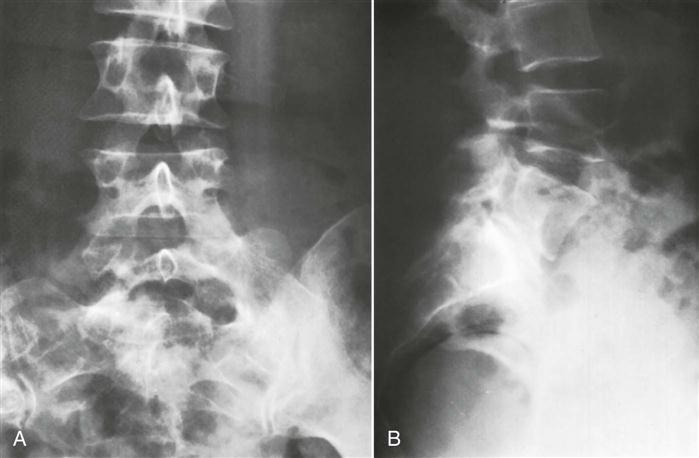

3. Disc spaces. Do they appear normal, or are there height decreases, as occurs in spondylosis?

4. Any vertebral deformity, such as a hemivertebra or other anomalies (Figures 9-100 through 9-103).

5. The presence of a bamboo spine, as seen in ankylosing spondylitis.

1. Any evidence of spondylosis or spondylolisthesis, which occurs in 2% to 4% of the population (Figure 9-107). The degree of slipping can be graded as shown in Figure 9-108.259 New grading or classification system involving lateral sacropelvic and spinopelvic balance have also been suggested.260

2. A normal lordosis. Do the intervertebral foramina appear normal?

3. Any wedging of the vertebrae.

5. Alignment of the vertebrae should be noted. Disruption of the curve may indicate spinal instability.

6. Any osteophyte formation or traction spurs (Figure 9-109).251,261 Traction spurs indicate an unstable lumbar intervertebral segment. A traction spur occurs approximately 1 mm from the disc border; an osteophyte occurs at the disc border with the vertebral body.